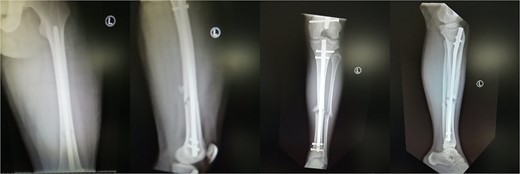

A 19-year-old male patient was admitted to the orthopedic department of our institution after a motorbike accident. The patient sustained a diaphyseal fracture of the left femur and ipsilateral tibia (floating knee) (Fig. 1), along with a right acromioclavicular joint type II injury and a right minimally displaced distal radius fracture. The patient was scheduled for emergent surgery. He underwent a retrograde intramedullary nailing of the left femur and an antegrade intramedullary nailing of the left tibia, under general anesthesia (Fig. 2). The operation was performed with the patient in the lithotomy position. The right intact leg was applied in 1000 of the hip flexion and 900 of the knee flexion. The duration of the surgery was 4 h and 20 min.

Post-operative view of the left femur and tibia. Concomitant retrograde IM nailing and antegrade IM nailing were performed.